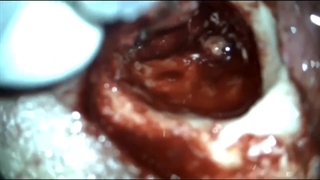

چگونگی عمل جراحی کلستئاتوم

در این ویدئو دکتر علی کوهی فوق تخصص جراحی گوش در مورد این موضوع توضیحات مفصل و مفیدی را در اختیار شما عزیزان قرار داده است.

کلینیک دکتر کوهی، یکی از مجرب ترین فوق تخصص های گوش، حلق و بینی و عضو هیئت علمی پژشکی دانشگاه تهران همواره آماده خدمت رسانی به بیماران محترم در زمینه انواع بیماری و جراحی های گوش است.